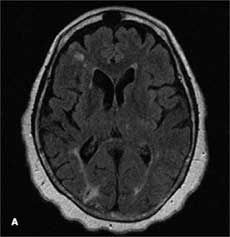

A previous transthoracic echocardiogram with a bubble study did not reveal any cardiac source of embolism. Axial MRI of the brain on admission showed an abnormal signal in the bilateral hemispheres representative of multiple subacute infarcts (Aand B); the right posterior frontal and right posterior parietal cortical and subcortical regions appeared to be most affected. A transesophageal echocardiogram revealed a severely thick atherosclerotic plaque with a large pedunculated mobile complex atheroma (C, arrow) in the upper descending aorta; the aortic arch showed severe atherosclerotic plaques with maximal thickness up to 10 mm (D).